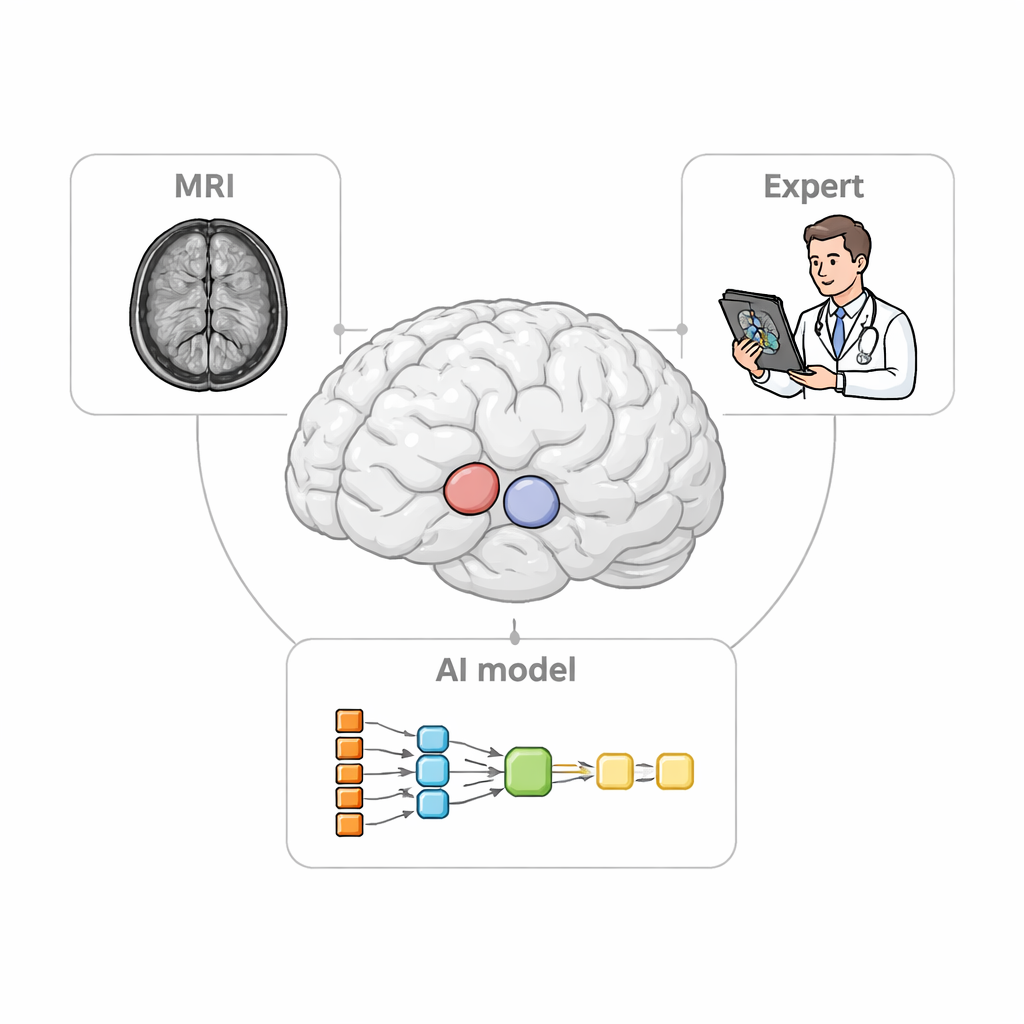

I ricercatori hanno progettato StriaSeg‑iARM come un sistema di deep learning in due fasi che lavora direttamente nello spazio cerebrale del singolo individuo anziché forzare la scansione in un modello standard. Nella prima fase il programma individua l’intero striato su una MRI tridimensionale. Nella seconda fase suddivide questa struttura in 12 sottoregioni definite anatomicamente su entrambi gli emisferi. Tra le due fasi sta l’innovazione chiave: un passaggio interattivo in cui un esperto può rapidamente verificare e, se necessario, correggere il contorno approssimativo prodotto dalla prima fase prima che venga eseguita la suddivisione più fine. Questo approccio combina la velocità dell’automazione con il giudizio di un osservatore umano formato.